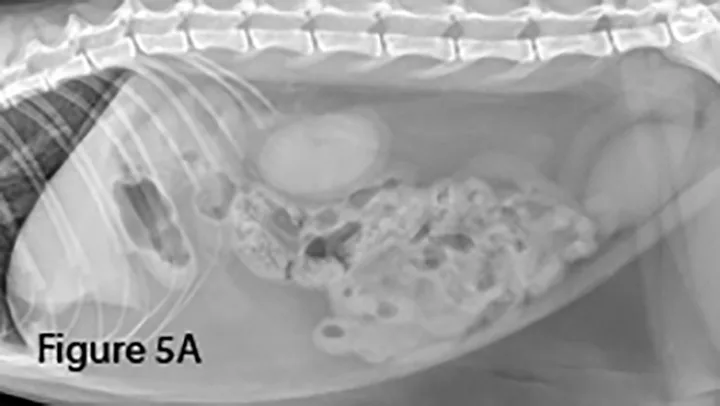

Linear foreign material often causes small bowel bunching, plication, or corrugation with or without severe intestinal dilation. String foreign bodies, more common in cats, can cause plication and/or corrugation, often without severe dilation. In dogs, cloth foreign bodies are more common and obstruction is often severe.

Lateral (Figure 5A) and ventrodorsal (Figure 5B) abdominal radiographs of a cat with string foreign body. Note the plicated (ie, ribbon candy) shape of small intestinal segments, bunched centrally. Pockets of triangular and odd-shaped abnormal intraluminal gas are present, common with linear foreign bodies.

To differentiate normal centralized small intestine from pathologic intestinal bunching, a plastic or wooden spoon may be used to place pressure on the lateral abdomen to disperse the intestinal segments. This cat demonstrated corrugation (ie, undulating serosal margins) of a segment of small intestine, seen in some cases of linear foreign body ingestion causing intestinal plication.